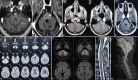

Figures